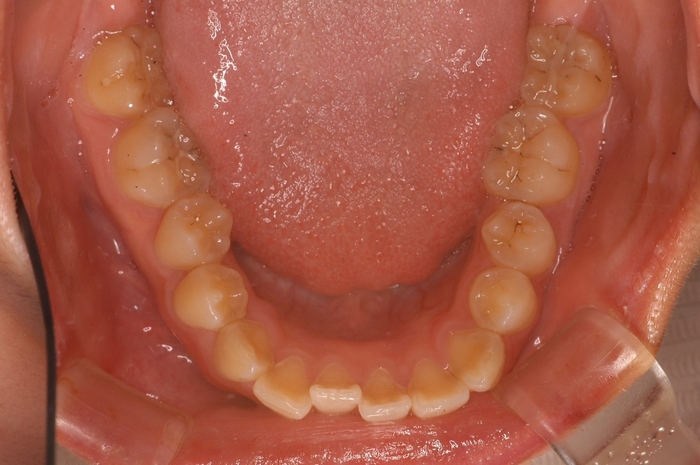

「理想的な歯並び」と「現代人に多い歯並び」の画像、これは何を意味しているのか?